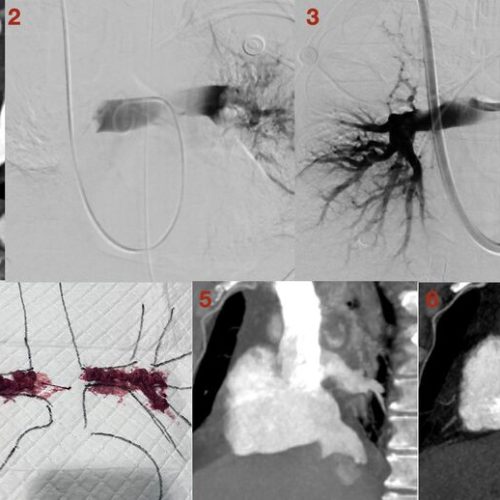

5-Year Milestone: PKU First Hospital’s World-Fi...

This article provides an in-depth analysis of a milestone case from PKU First Hospital: the world's first "Portal-end Embolization combined with TIPSS" procedure performed in 2021. Facing an extreme hepatic...